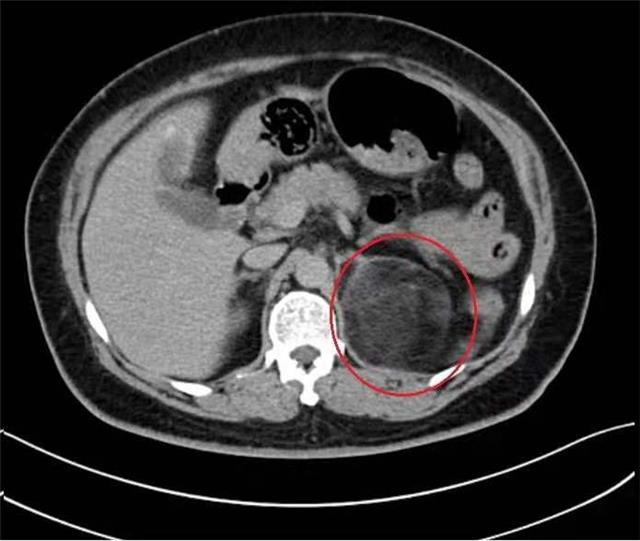

从影像学上看,患者病变肾上腺已压迫同侧的肾脏,如此巨大的瘤体实属罕见,与其说肾上腺上长瘤子,不如说瘤子上长了个肾上腺,且瘤体与周围血管贴合严密,不排除有严重粘连的可能。